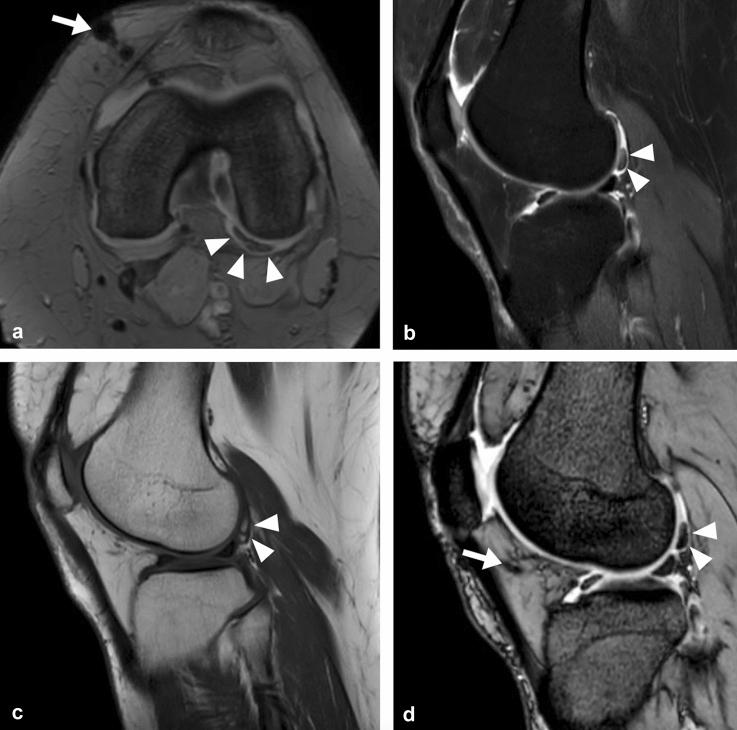

This study aims to assess the effectiveness of Microfragmented Autologous Fat Tissue (MFAT) treatment for knee osteoarthritis and to investigate whether patients' pre-treatment clinical condition, such as synovitis, correlates with clinical outcomes, to identify potential predicting factors for the success or failure of the treatment.

METHODS

In this prospective Cohort Study Level II multicentric trial, consecutive patients with a diagnosis of early/mild osteoarthritis and failure of previous conservative measures were enrolled to undergo diagnostic arthroscopy and a single MFAT injection. Patients were assessed with repeated scoring systems at baseline, 6 months, and 12 months after surgery. The demographic features, the arthroscopic findings, the immunophenotype of injected tissue and the histologic examination of synovia of failed patients were analyzed.

RESULTS

Data from 91 patients showed a significant improvement in Lysholm, WOMAC scores at 1-year follow-up (p < 0.001). A significant decrease in VAS score was observed, while a significant improvement of measured flexion angle was registered at 1 year (p < 0.001). No major complications were reported. Age and synovitis were identified as significant factors influencing the clinical outcome (p < 0.05). Body mass index, previous or concomitant procedures, and specific cartilage defects had no influence. The mean number of injected adipose tissue-derived mesenchymal stem cells seem not to correlate with the clinical outcome.

CONCLUSION

MFAT is effective in reducing pain when used with a single dose injection in early/mild OA of the knee, without major complications. Age over 60 and synovitis may be predictive for persistent pain at one year and should be considered before indications.